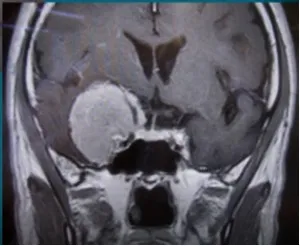

鞍区位于颅底的正中位置,因为其形状酷似马鞍而得名。它的面积相当有限,却如同一个超级复杂的神经血管枢纽,高度密集地“驻扎”着非常重要的颅内结构——垂体是人体关键的内分泌腺体,...